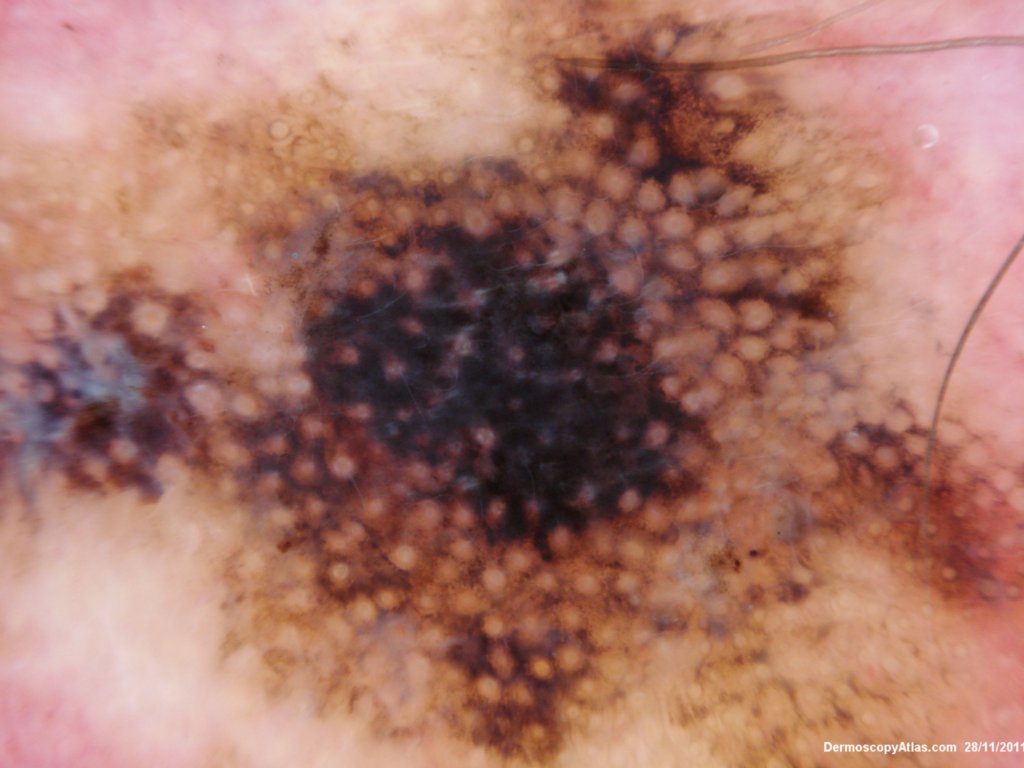

Site: Ear lobe

Diagnosis: Lentigo Maligna

Sex: M

Age: 86

Description: Pigmented lesion on the ear

This elderly male had a pigmented lesion on his ear which was shown to be a lentigo maligna but surgery was refused. It progressed over 5 years as shown but remained a lentigo maligna or melanoma in situ. There is marked perifollicular pigmentation with black structureless areas where the melanoma has obliterated the follicles. Sometimes the terms annular granular structures and rhomboid figures are used along with asymmetrical perifollicular pigmentation to describe these earlier changes. In truth grey circles are often the earliest features of lentigo maligna particuarly on the face.